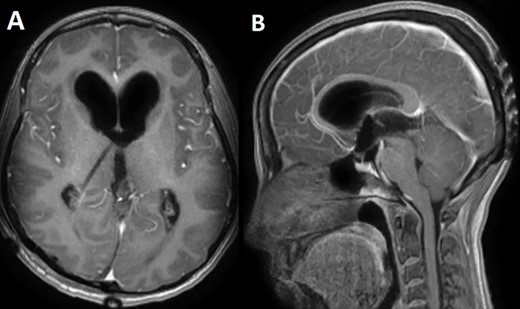

A 33-year-old lady presented to the clinic for bilateral retro-orbital headache with tinnitus most severe upon waking up in the morning for 3 months, without evidence of nausea, vomiting, or insomnia. Vital signs were within the normal range. The neurologic exam was non-focal. Enhanced brain magnetic resonance imaging (MRI) revealed a T1 hypointense, T2 hyperintense, homogenously enhancing Pineal tumor of 2 × 1.89 × 1.61 cm (anteroposterior × transverse × height) compressing the posterior wall of the third ventricle with evidence of moderate hydrocephalus (Fig. 1). The patient was scheduled for craniotomy for resection of the mass. In the operating room, an external ventricular drain was inserted in the right occipital horn followed by craniotomy and resection of the mass through a right occipital transtentorial approach. Gross total surgical resection was achieved under microscopic navigation (Fig. 2). The patient was extubated. Upon extubation the patient started to have chewing-like movement of her lips on the ET tube, afterward, she was transferred to the intensive care unit for monitoring. On postoperative day 1, we noticed that the patient was still having chewing-like movements typical of orofacial dyskinesia with evidence of buccal mucosal injury and swelling of the lips (Video 1). She was also complaining of inability to sleep. The patient was on regular postoperative medications (esomeprazole, cefazolin, paracetamol, morphine, dexamethasone, levetiracetam). An enhanced postoperative brain MRI was done for evaluation and confirmed complete resection of the lesion without any bleeding or ischemic changes (Fig. 3). The chewing like movements lasted for 72 hours and spontaneously resolved afterward. Pathology confirmed pineal parenchymal tumor of intermediate differentiation (WHO Grade III). The patient was treated with adjuvant radiotherapy. This is an unreported complication post pineal gland tumor resection in humans. Below we review the literature reporting abnormal facial movements associated with various pineal gland conditions as the data remains scarce concerning dyskinesia post pineal tumors resection in humans.

T1 enhanced axial (A) and sagittal (B) MRI showing a T1 hypointense homogenously enhancing pineal tumor.